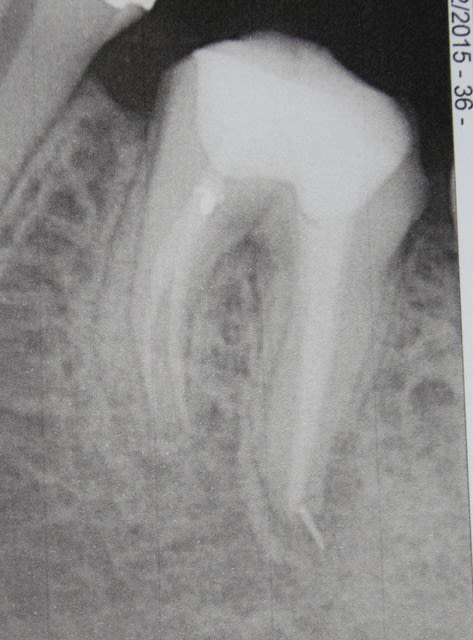

Blette

avant dubai et avant pose de couronne, dent reconstituée avec un tenon scellé, je n ai pas deposé pour eviter de fragiliser plus la racine, il y avait une reconstitution composite étanche non radio opaque , il s'est écoulé un an entre la premiere radio avec devis et l'empreinte a ete faite l annee suivante (2013) aucun signe pendant 1 an

Dsc 0227  2  bvu1y3 - Eugenol